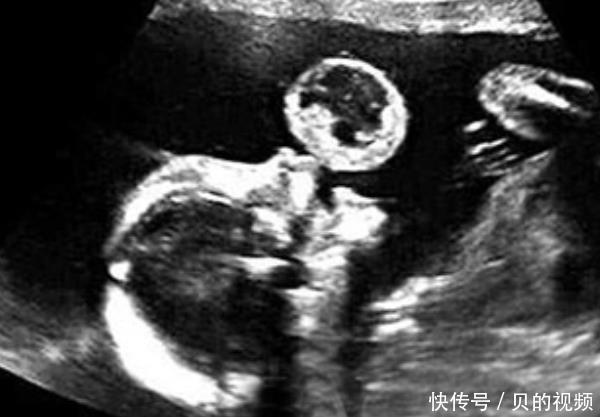

实际上,怀孕后,有些人会继续呕吐,而另一些人从未呕吐,其原因直接与未出生的婴儿有关。在现实生活中,许多孕妇都会有妊娠反应,通常每个人都会认为妊娠反应是正常的。

1.孕吐少,胎儿发育稳定

许多怀孕的母亲发现他们怀孕后根本没有反应。和平时期没有区别,如果不是去医院确认怀孕。您可能不相信自己在怀孕。那么为什么没有怀孕反应呢?医生说:没有怀孕的事实仅意味着腹部的婴儿发育良好且稳定。因此,怀孕期间的反应非常强烈,表明腹部的婴儿相对不稳定。因此,在怀孕期间没有反应的怀孕母亲说,腹部的婴儿发育良好且非常稳定,这是非常受欢迎的事情。